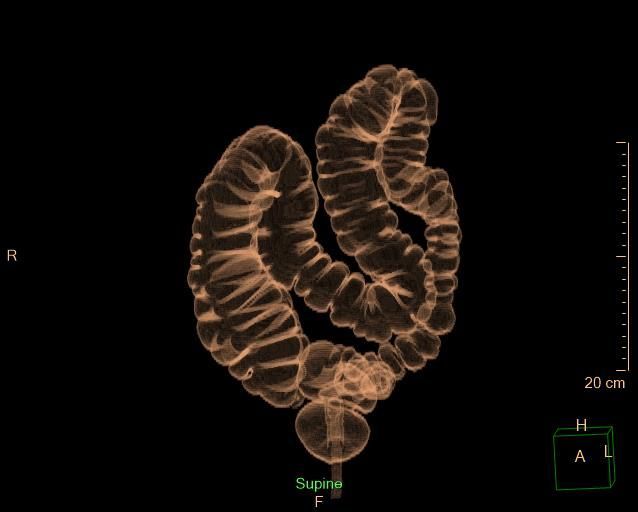

- Virtual colonoscopy uses CT scanning to obtain an interior view of the colon.

Virtual colonoscopies are a more thorough, less invasive form of the traditional colonoscopy because there’s only a 2.5″ insertion. The danger of tearing or perforating the colon walls is removed, and because it’s minimally invasive, there’s no need for anesthesia, eliminating another potential risk.

The images produced from our scans are reviewed by a board-certified radiologist, and a report is created for our patients to share with their physicians.